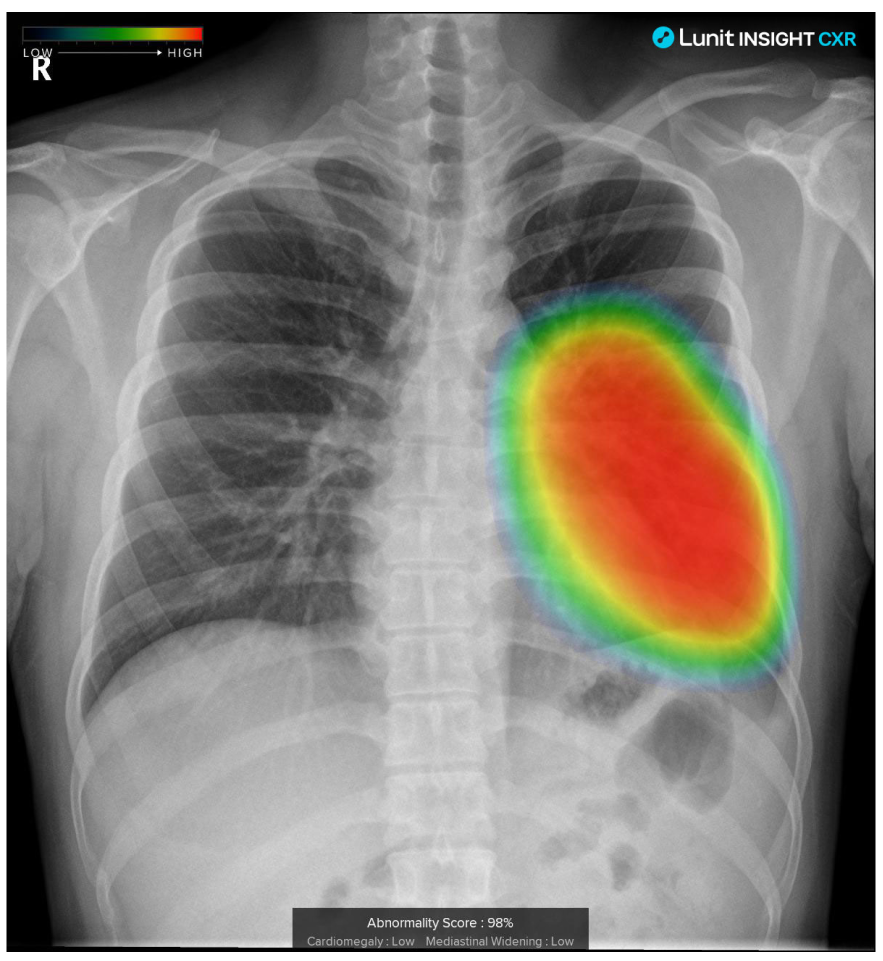

Одной из самых перспективных областей применения ИИ в медицине является диагностика. Нейросети способны анализировать медицинские изображения (рентген, КТ, МРТ) с невероятной точностью, выявляя даже самые незначительные отклонения от нормы. Обучившись на миллионах снимков, ИИ оказывается способен достоверно обнаруживать закономерности и аномалии, невидимые даже для опытного человеческого глаза.

Основанная на ИИ система Lunit INSIGHT CXR анализирует рентгеновские снимки и выявляет признаки различных заболеваний, включая пневмонию, туберкулез и рак легких. Система включена в программу обязательных скринингов по онкологии во многих странах.